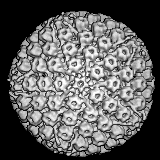

Izquierda: estructura de herpesvirus; derecha: foto de herpesvirus humano